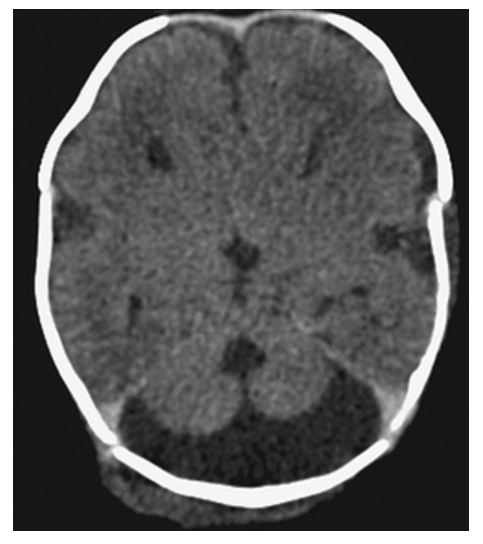

Hydrocephalus. T1-weighted axial MRI shows markedly dilated lateral ventricles with low-signal CSF.

Hydrocephalus. T2-weighted axial MRI shows high-signal CSF of the markedly dilated lateral ventricles.

Hydrocephalus. Axial NECT shows markedly dilated lateral ventricles.